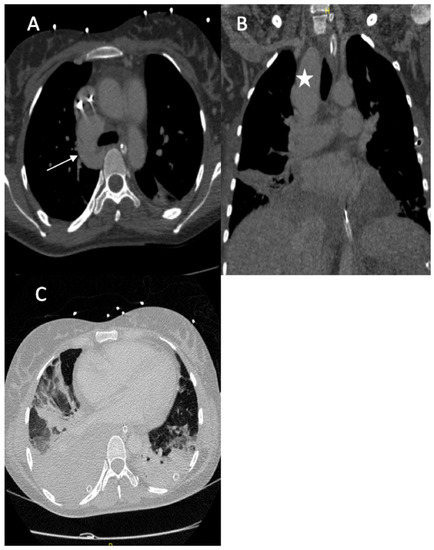

A 36-year-old female was referred to our hospital presenting with hemoptysis and respiratory distress. One week before she delivered (35 weeks gestation), she experienced hemorrhagic shock due to the rupture of a splenic artery pseudoaneurysm. She was treated by a cesarean birth and a splenectomy. The patient was managed using mechanical intubation and bilateral pleural drainage. An enhanced thoracic computed tomography (CT) scan revealed an intraparenchymal hemorrhage in the right upper lobe with an arteriovenous fistula between the apical segmental pulmonary artery and the azygos vein, as well as a pseudoaneurysm at the ostium of the middle segmental artery (Figure 1).

Figure 1.

(A) Axial image from the contrast-enhanced thoracic CT scan revealed an arteriovenous fistula between the apical segmental artery and the azygos vein (arrow); (B) coronal section of the CT scan revealed a pseudoaneurysm of the right lobe superior artery (star); (C) axial image thoracic CT scan (pulmonary window) showed bilateral pleural effusions with ground glass opacity, most likely due to pulmonary hemorrhaging.